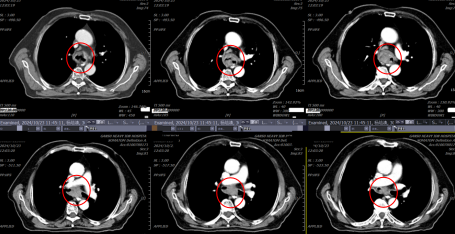

患者杨某,男,82岁,四川省成都市人,出现胸闷、气短2周。2024-10-21患者突发胸闷、气短加重,伴痰中带血,CT检查提示气管隆突区见软组织结节影,形态欠规则,较大截面约2.6cmx2.7cm,邻近气管壁稍增厚,局部管腔变窄。华西医院行支气管镜检查:气管下段隆突处菜花样新生物阻塞致气管下段左侧壁、右侧壁线性狭窄;支气管镜无法继续观察双侧各级支气管结构,镜下活检出血风险较大。华西医院的医生认为患者年纪大,取病检困难,肿瘤已引起严重的呼吸困难,各种治疗方法都无法进行,只建议可以放个支气管支架。

治疗前20241121增强CT片(红圈内为气管肿瘤)